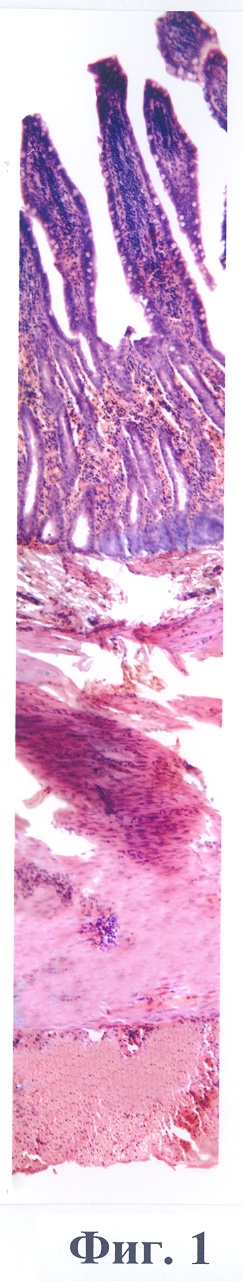

Данный пример иллюстрирует фиг.1, где представлена гистоструктура стенки тонкой кишки кошки №2 через 2 часа после наложения матерчатых полос на участок кишечника. Окраска гематоксилин и эозин. Объектив х10. В слизистой оболочке определяется выраженное паретическое расширение капилляров с имбибицией окружающей сосуды ткани эритроцитами, в ворсинах большое количество нейтрофильных лейкоцитов. В подслизистой и гладкомышечной оболочках выявляются очаговые и диффузные диапедезные кровоизлияния, в расширенных сосудах – краевое стояние нейтрофильных лейкоцитов с выходом их за пределы сосудистой стенки, образованием очаговых лейкоцитарных воспалительных инфильтратов. Определяется выраженная зернистая дистрофия гладких миоцитов.